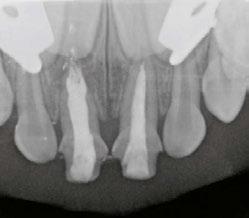

My first “ah-ha” moment came when I saw the closing of a long-standing large sinus tract on my pediatric 8-year-old patient, who after trauma presented with chief complaint of mobility, swelling, and likely a situation that looked hopeless. The biggest challenge with an open apex case is productive disinfection followed by creation of a long-lasting seal. Calcium hydroxide was used as the intracanal medicament between visits. Because it was not radiopaque, it was hard to gauge if it even made critical contact with the periradicular biofilm. I placed a CollaPlug® scaffold gingerly, visualizing with the microscope and then placed the MTA on the CollaPlug pillow taking several radiographs until I felt that I could see the MTA appear to encapsulate the irregularly shaped apex. Despite the visually satisfying post-op radiograph, I would come to see the amazing periapical healing complete with a rejuvenation of the periodontal ligament and concomitant osseous healing.

I don’t remember the first time I actually used MTA for an apexogenesis in my private practice, but the circumstances were always the same. I would get a call regarding a fracture to a front tooth with a pulp exposure on an 8-year-old child. If I couldn’t see that child that day, I would instruct my referring dentist to gently cover the pulp exposure with GIC and refer to me ASAP. The protocol required removing a minimum of 2 mm of pulp tissue or until any bleeding stopped. I would use a diamond in a high speed with copious irrigation. Gently disinfecting with chlorohexidene and placing a saturated cotton pellet to assess healthy pulp was critical followed by placing a 2 mm thickness of MTA as a direct pulp cap. In those days, I would place a wet cotton pellet on top of the MTA and seal with Cavit™ per manufacturer’s recommendations. I would then bring the patient back to confirm set of the MTA, absence of symptoms, and do the definitive coronal restoration.

Whether it was a traumatic pulp exposure or a carious pulp exposure on an asymptomatic child with under developed roots, I was seeing consistent success. The patient was remaining asymptomatic because the pulp vitality and health was maintained. I was further rewarded with being able to see that beautiful dentin bridge that developed underneath the MTA protecting that healthy pulp as the root grew in length and closed.

With trauma protocols, we recall these patients quarterly for the first year prepared to intervene with traditional endodontic treatment anytime we see evidence of failure. We then see these patients annually for 5 years, or more often, until I am satisfied that the root growth is complete. Unfortunately, I was starting to see an ugly silver gray halo at the cervical margin as a result of the tooth erupting out of the alveolus as part of the normal growth of the child. All of a sudden, I was faced with another treatment challenge. Now I had to take out my minimalistic composite, remove MTA, and then remove tooth structure to facilitate non-vital bleaching. I remember being very frustrated that we were weakening tooth structure coronally after working so hard to grow the root. I also faced the possibility of damaging the pulp as we had to remove much of that 2 mm MTA cap.

Figures 1 and 2: Example of staining from traditional MTA, non-vital bleaching after Figure 3: Pre-op Figures 4 and 5: Pulp cap Figures 6: Apexogenesis

Figures 7 and 8: Recall 1 and 2 Figure 9: Recall 3 Figure 10: EndoSequence BC RRM